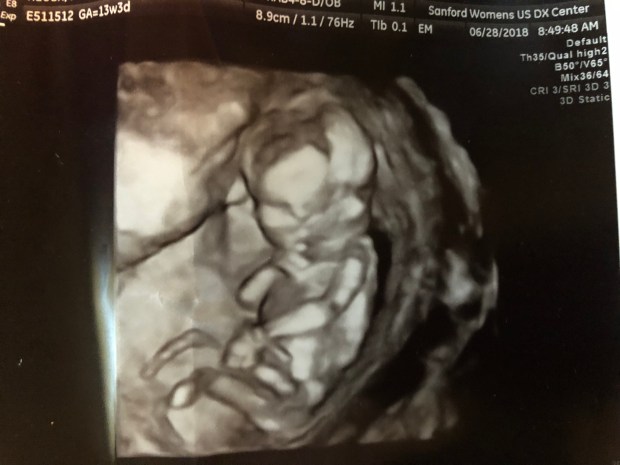

Then came the fun part, our 15-20 minutes looking at our baby!

But it was there instantly!  I didn’t need to search for the beautiful flicker because it showed up right on queue, plain as day, and lit up the screen for me!  Throughout the entire scan, it was almost all I could look at, that marvelous flickering organ!  Our baby continued to have a pulse and be alive and that was my biggest concern that day!

I watched our baby squirm and dance on the screen in front of us and tears began to stream down the sides of my face.  These were the happiest of tears!  I shared with the tech a little of our history and about our loss and just how good this scan made me feel!  She kept the wand on my stomach awhile longer so we could watch our growing child show off the incredible abilities they already have, my eyes glued to their heartbeat.  I said a silent prayer, thanking God that today was another good visit and prayed that this child would have a strong and healthy future ahead of them.